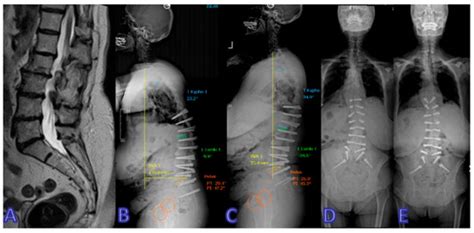

Dynamic vs. Rigid: Transforming the Treatment Landscape for ...

mdpi.com